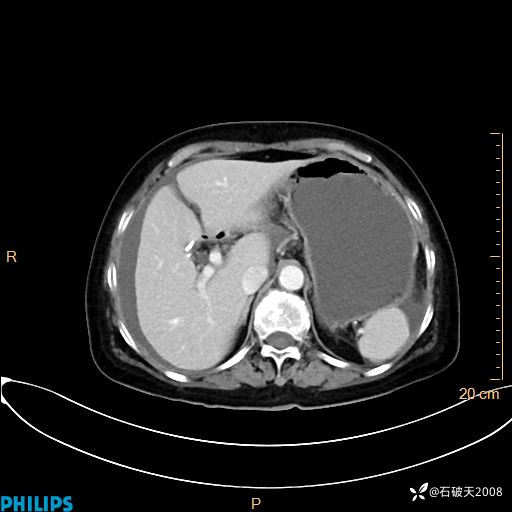

静脉期